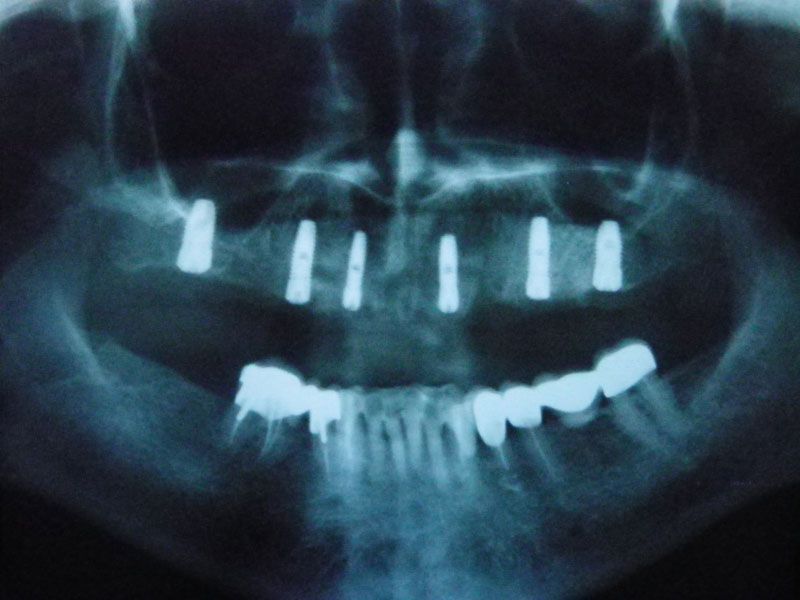

Через 10 недель, после 3D-моделирования и подробнейшего планирования, была проведена операция установки имплантов в позиции опорных зубов. Нужно отметить, что операция, несмотря на объем, была малоинвазивной: импланты были подобраны таким образом, что не потребовалось проводить обширных костных пластик.

Протезирование было проведено с помощью трех мостовидных протезов, причем выбор цвета и формы зубов был предоставлен пациенту. Оказалось, что высоко-эстетичнын зубы, были мечтой пациентки всю жизнь. Они и были выбраны. Диссонанс с собственными зубами, которыми так дорожила наша пациентка до операции, оказался столь сильным, что теперь в планах пациентки заняться нижней челюстью в плане функционально-эстетическойй реабилитации фронтального участка несъемным протезированием на имплантах.